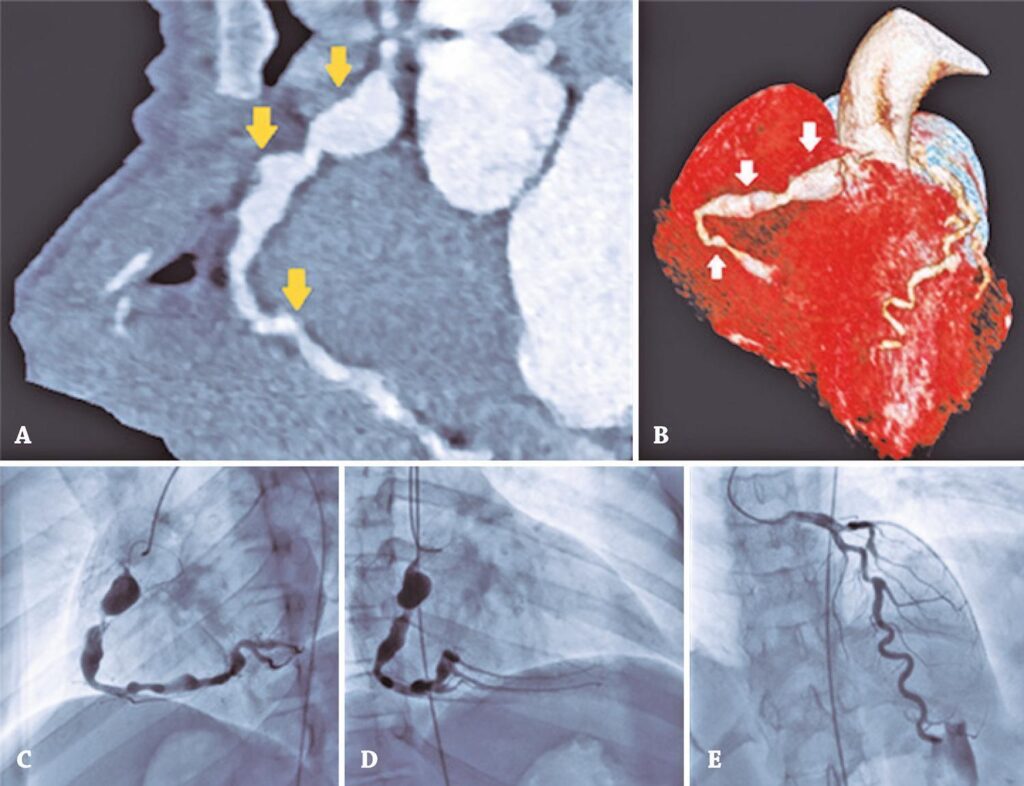

Um paciente do sexo masculino, 11 anos de idade, com história clínica de atraso no desenvolvimento psicomotor e pré-excitação ventricular, exigiu diversas consultas de retorno em outros serviços. Não foram descritos outros sintomas cardiovasculares associados. Como a família mudou o local de residência, a criança foi encaminhada para nosso hospital. Um ecocardiograma transtorácico (TTE) foi realizado como parte da avaliação inicial padrão na primeira consulta e mostrou alterações anatômicas das artérias coronárias. Outras investigações incluíram tomografia computadorizada (TC) do coração, que revelou diversas dilatações aneurismáticas ao longo da artéria coronária direita (CD), a maior medindo 10x10mm, no segmento proximal (Figura 1A). Realizou-se cateterismo cardíaco, e cinco aneurismas foram identificados na CD: um mais proximal (18x11mm); um gigante, no terço médio (7x20mm); e três mais distais (5,2mm; 5,5mm e 6mm de diâmetro) (Figuras 1C e 1D). A artéria coronária esquerda apresentou ectasia relevante (diâmetro proximal de 3mm; diâmetro distal de 5,4mm) do tronco, com estenose de 50% no terço médio da artéria descendente anterior (Figura 1E).